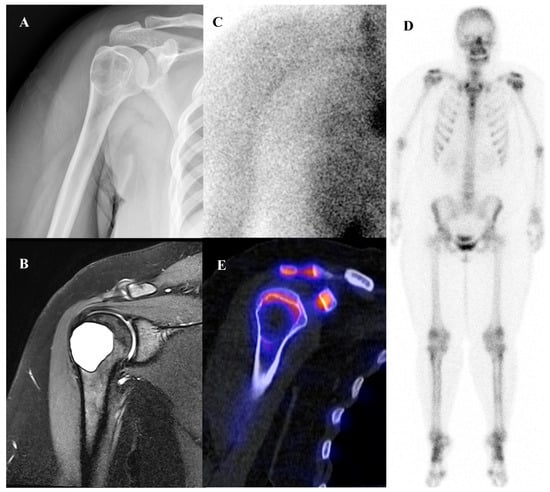

Patients with Ewing sarcoma are at high risk for disease recurrence, which most often occurs in the lungs or bone and carries a poor prognosis [45,46]. [18F]FDG PET/CT is an extremely valuable tool for post-treatment surveillance and for the early detection of recurrent disease [18,25]. The appearance of new, focal [18F]FDG-avid lesions on follow-up scans is highly suspicious for recurrence and prompts further investigation and salvage therapy. Whole-body nature of [18F]FDG PET/CT is ideal for detecting recurrence at any potential site. Figure 2 demonstrates a representative case in which bone scintigraphy failed to reveal recurrent disease, whereas [18F]FDG PET/CT clearly identified the metabolically active presacral mass, subsequently confirmed as recurrent Ewing sarcoma after surgical excision.

Figure 2.

A 19-year-old female with recurrent Ewing’s sarcoma. (A,B) Bone scintigraphy shows no abnormal uptake on both anterior and posterior view. (C) T1 fat-suppressed magnetic resonance imaging demonstrates a lobulated, enhancing presacral mass with invasion of the sacrum. (D–F) [18F]FDG positron emission tomography/computed tomography reveals intense uptake of the mass (SUVmax 9.0). Surgical excision confirmed recurrence of Ewing’s sarcoma.